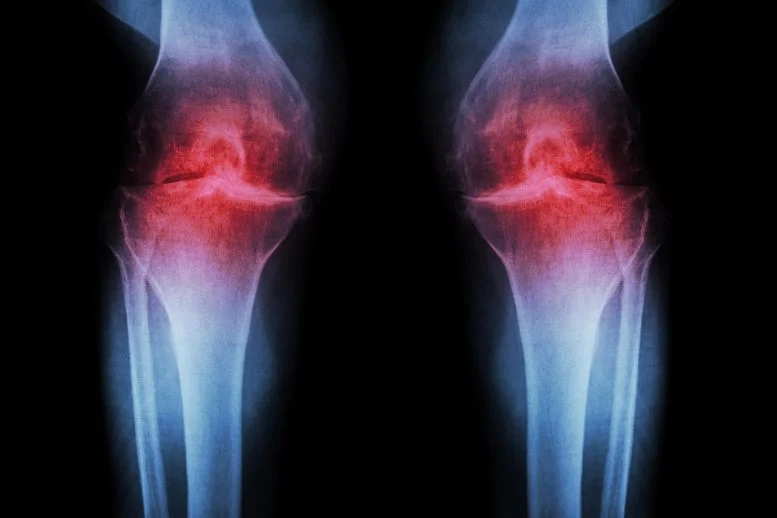

Το Anti-Aging Injection αναζωογονεί τον χόνδρο του γόνατος και προλαμβάνει την αρθρίτιδα

Μια θεραπεία που μπλοκάρει έναν σχετιζόμενο με την ηλικία αποκατεστημένο χόνδρο σε γήρανση και τραυματισμένες αρθρώσεις επαναπρογραμματίζοντας τα υπάρχοντα κύτταρα αντί με τη χρήση βλαστοκυττάρων. Ερευνητές στο Stanford Medicine αναφέρουν ότι η παρεμπόδιση μιας πρωτεΐνης που συνδέεται με τη γήρανση μπορεί να αποκαταστήσει τον χόνδρο που φθείρεται φυσικά στα γόνατα των ηλικιωμένων ποντικών. Στη μελέτη, η ενέσιμη θεραπεία όχι […]